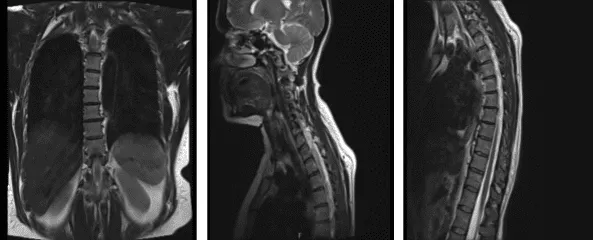

MRI-3T Columna torácica sin contraste

Estructuras osas: La alineación de la columna torácica es anatómica. No hay deformidades por compresión. La señal de la médula ósea es en general adecuada para la edad. Tejidos blandos paraespinales: Los tejidos blandos paraespinales visualizados son muy poco destacados.

Discos intervertebrales: Hernias discales paramedianas izquierdas presentes en los niveles T6-T7 que impactan las raíces nerviosas C7 izquierdas que salen, causando una leve estenosis del canal espinal. No hay estenosis del canal espinal. Los forámenes neuronales están patentados.

Médula espinal: No hay zonas de anomalía de señal focal en la médula espinal torácica. El cono medular termina en el nivel T12 y se encuentra dentro de los límites normales. La hernia del disco paramediano izquierdo a nivel T6-T7 causa un efecto de masa leve en las raíces nerviosas C7 izquierdas existentes.